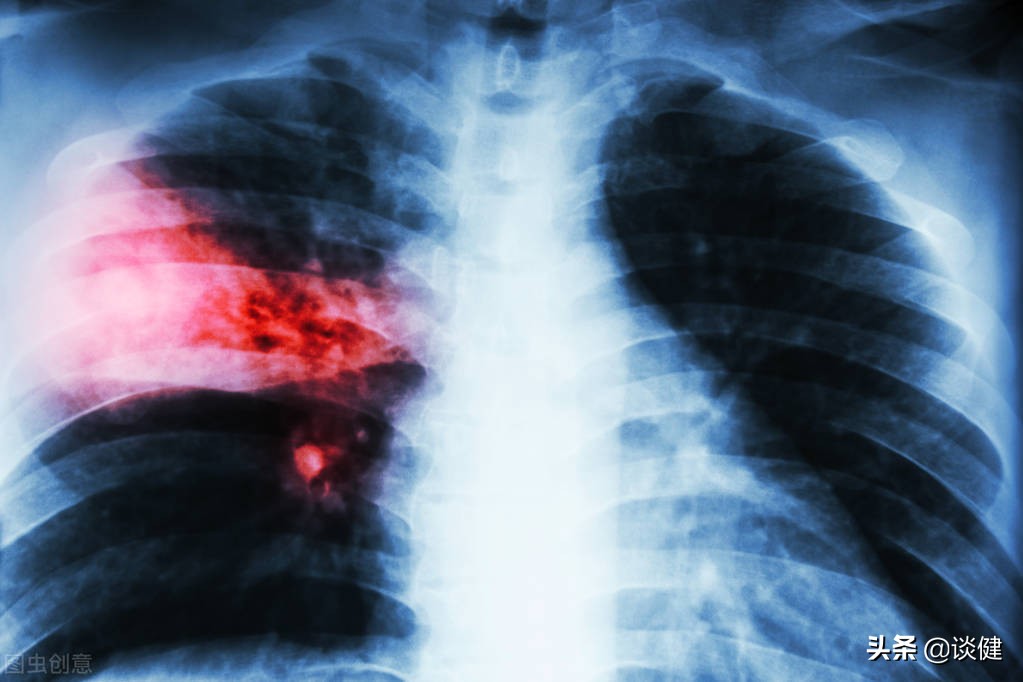

一般被认为是“感冒时容易发生的疾病”。事实上,典型肺炎的早期症状,如发烧、寒战、咳嗽和咳痰,与感冒非常相似。但是,与感冒不同的是,肺炎是当身体的抵抗力下降时感染细菌和病毒引起的疾病。最常见的感染是肺炎链球菌,约占30%,但还有许多其他病原体,如流感、支原体、衣原体、链球菌和金黄色葡萄球菌。而且普通的感冒药对这些细菌和病毒都不起作用。

随着气温的下降,老年人由于免疫力下降,很容易受到病原菌的攻击,从而让自己趋于罹患肺炎的高风险之中。实际上,在临床上一到冬季,老年人因肺炎住院的也是越来越多。如果老年人感染了肺炎却认为自己感冒了,不管不顾,肺炎会迅速恶化,引起呼吸窘迫,甚至死亡,所以要小心。

随着年龄的增长,老年人的吞咽能力明显受损,食物和饮料经常进入气管,而不是食道,从而导致患病。如果食物和饮料中含有的细菌和唾液中的细菌通过气管进入肺部,很可能会发生吸入性肺炎。一旦病情严重,很容易引发呼吸衰竭。